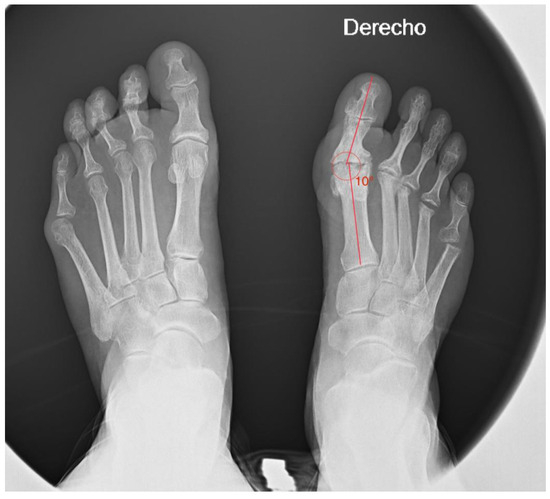

Clinical examination reveals a varus deviation of the first toe and claw position of the lesser toes (Figure 1). Manual reduction of the varus is not possible, and movement of the hallux is painful. In addition, the position of the hallux prevents the patient from putting on shoes normally.

Finally, the radiological study aids in assessing the degree of deformity and the condition of the joints (Figure 2). It also provides insight into the surgical techniques previously employed. It is likely that her prior surgery involved a Silver exostectomy technique combined with soft tissue release, which contributed to the current condition of the toe. Evidence of a Silver exostectomy is also observed on the fifth metatarsal head.

Figure 2. Preoperative anteroposterior (AP) weight-bearing radiograph of both feet demonstrating significant hallux varus deformity and associated structural abnormalities in the lesser toes.